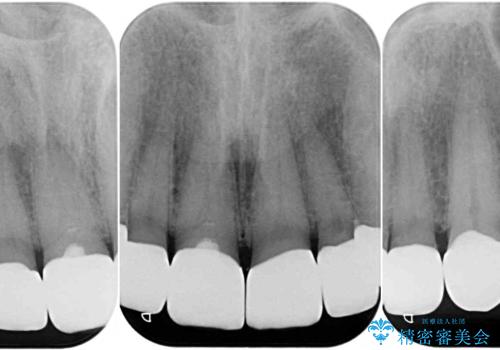

- 前歯のテトラサイクリンによる変色歯と、レジン充填の色の違いを気にして来院された患者様です。

患者様の希望により、前歯6歯をオールセラミッククラウンにて補綴することとしました。